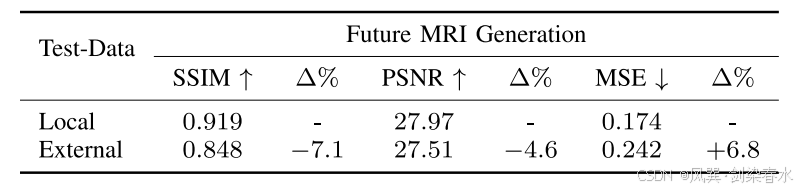

Table 1 | 测试集结果:

Table 2 | 治疗天数定量结果:

Table 3 | 内部测试与外部测试之间的性能比较: